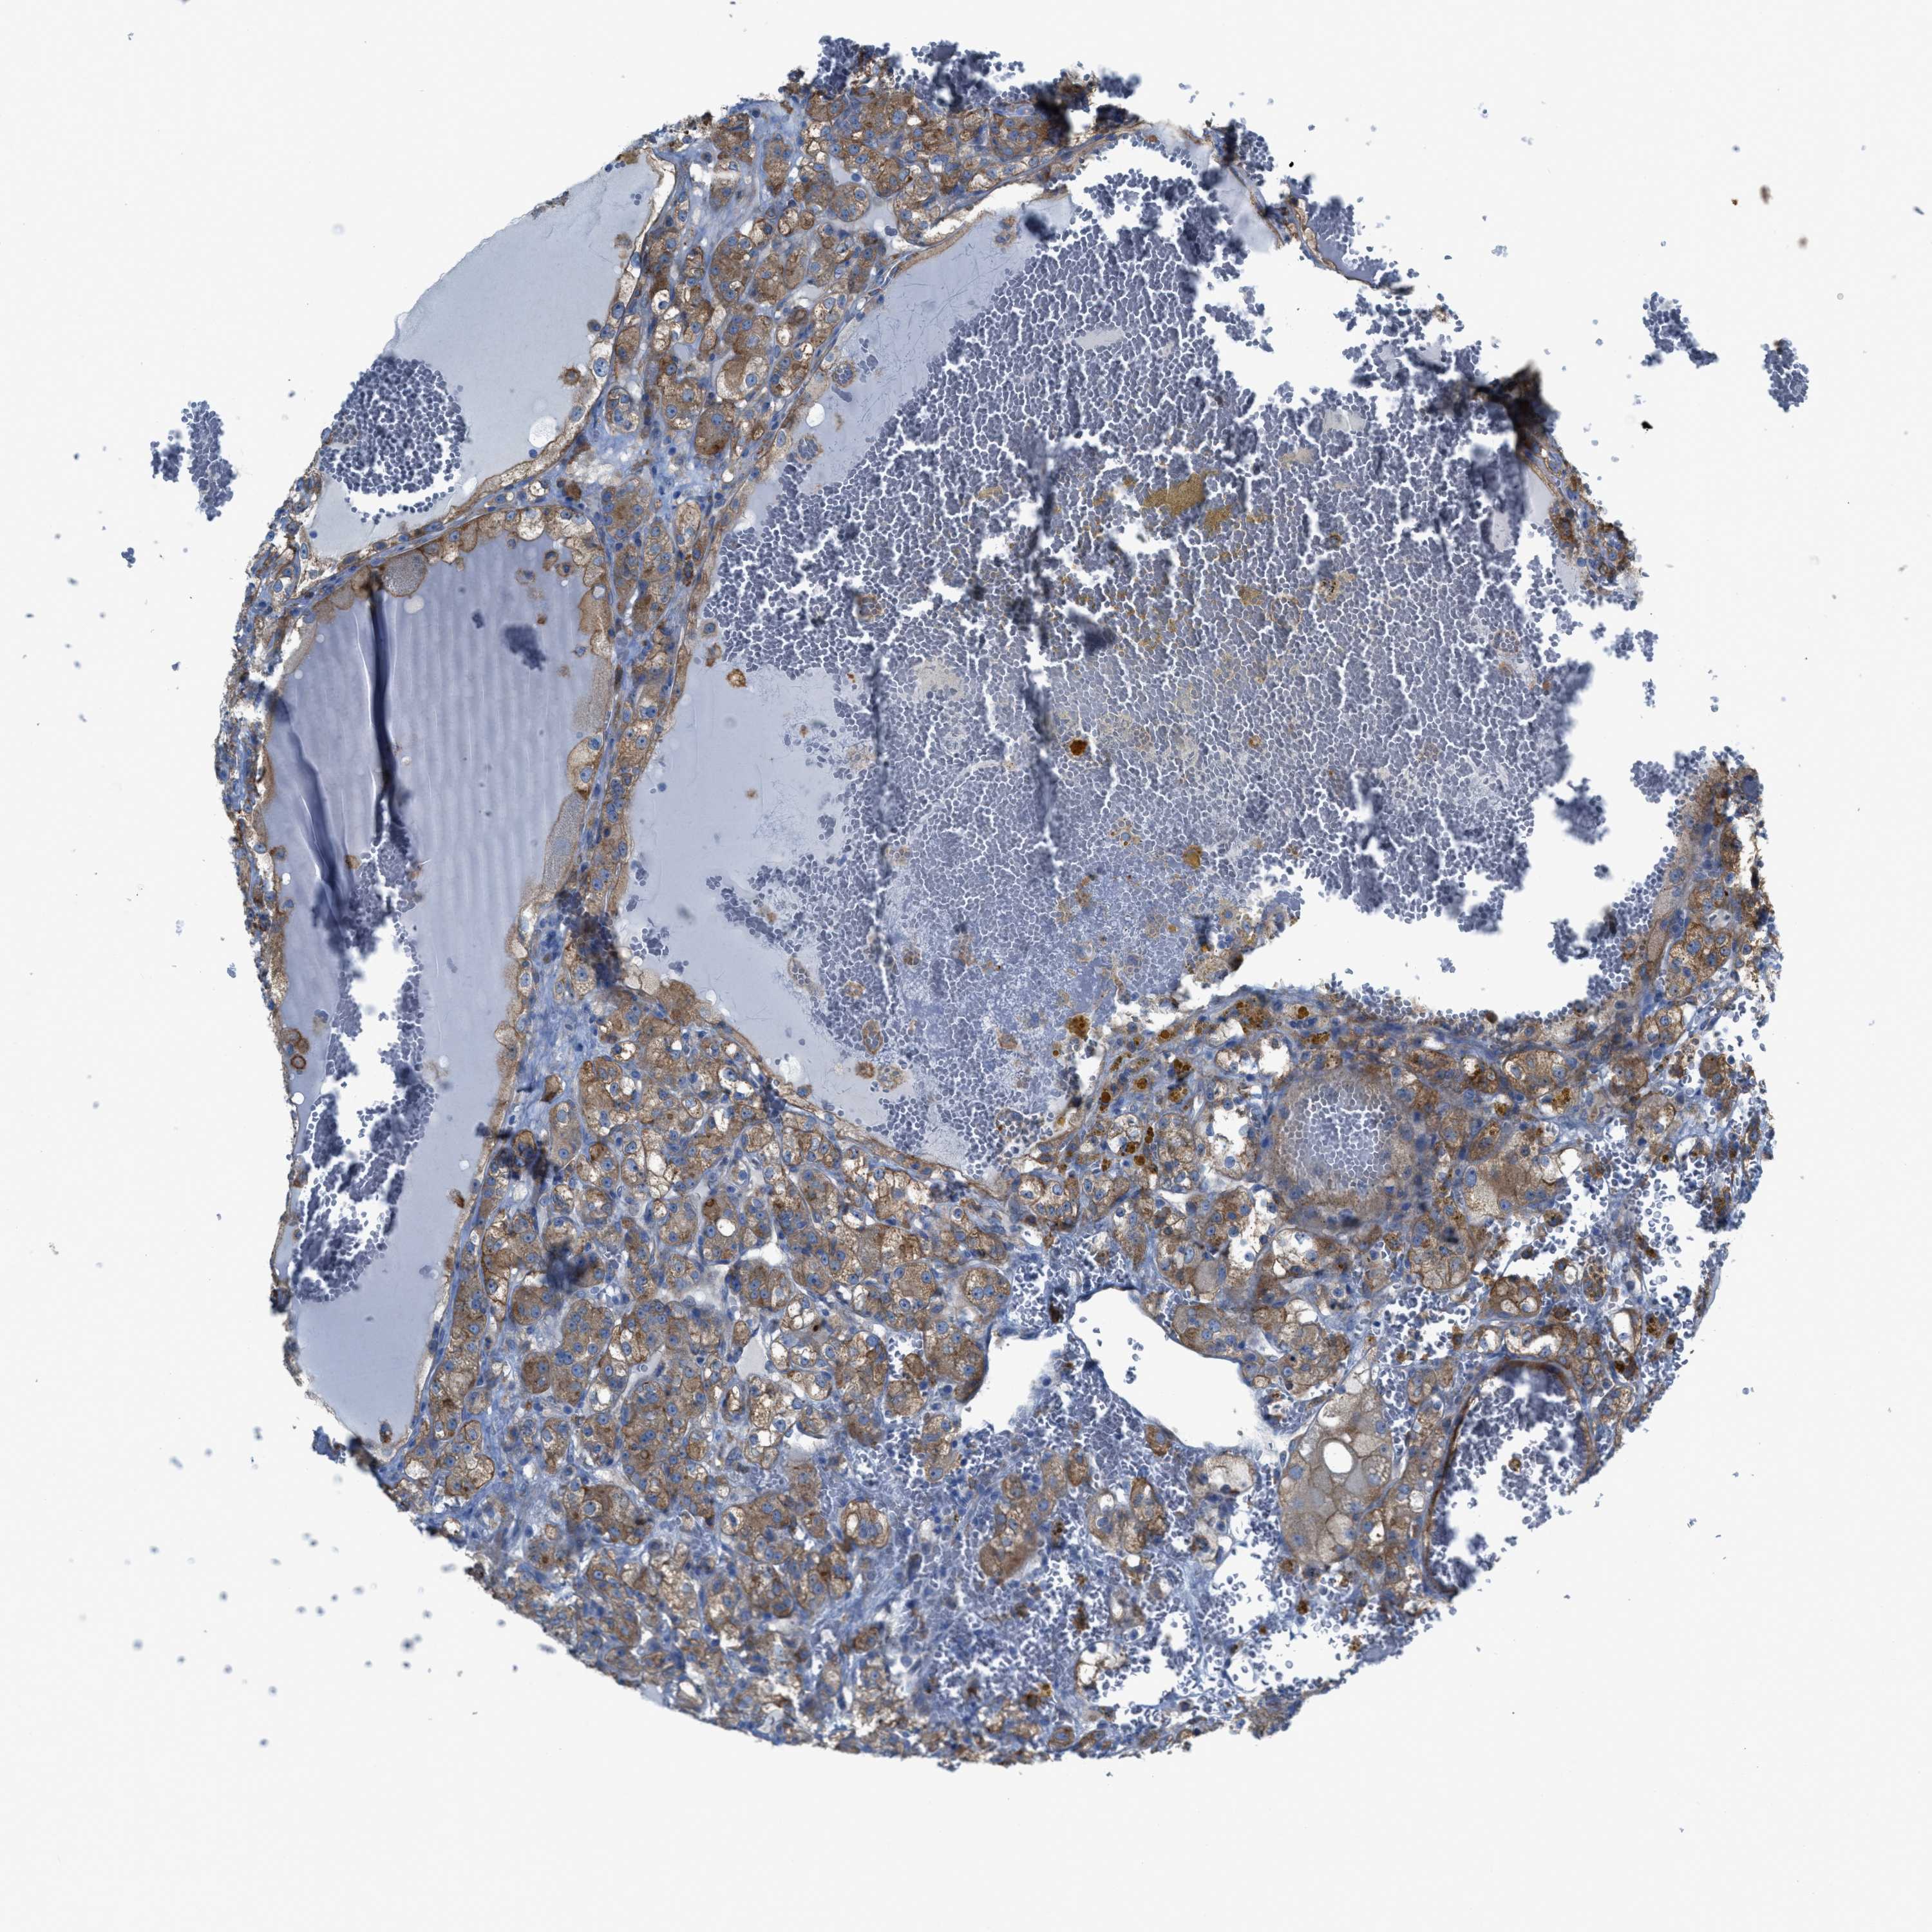

KIDNEY RENAL CLEAR CELL CARCINOMA (VALIDATION) - Interactive survival scatter ploti

The Survival Scatter plot shows the clinical status (i.e. dead or alive) for all individuals in the patient cohort, based on the same data that underlies the corresponding Kaplan-Meier plots. Patients that are alive at last time for follow-up are shown in blue and patients who have died during the study are shown in red.

The x-axis shows the expression levels (FPKM) of the investigated gene in the tumor tissue at the time of diagnosis. The y-axis shows the follow-up time after diagnosis (years). Both axes are complimented with kernel density curves demonstrating the data density over the axes. The top density plot shows the expression levels (FPKM) distribution among dead (red) and alive patients (blue). The right density plot shows the data density of the survived years of dead patients with high and low expression levels respectively, stratified using the cutoff indicated by the vertical dashed line through the Survival Scatter plot. This cutoff is automatically defined based on the FPKM cutoff that minimizes the p-score. The cutoff can be changed by dragging the vertical line or by entering a cutoff value in the square labeled "Current cut-off".

Under the Survival Scatter plot the p-score landscape (black curve; left axis) is shown together with dead median separation (red curve; right axis). Dead median separation is the difference in median mRNA expression between patients who have died with high and low expression, respectively. It is calculated as follows: median FPKM expression of dead patients with high expression - median FPKM expression of dead patients with low expression. This is intended to aid the user in visually exploring custom cutoffs and the associated p-scores and dead median separation.

Individual patient data is displayed and can be filtered by clicking on one or more of the category buttons on the top of the page. Categories describing expression level and patient information include: high, low, alive, dead, female, male and tumor stages. The scale of the x-axis can be toggled between linear and log-scale by clicking on the "x log" button. Mouse-over function shows TCGA ID, patient information and mRNA expression (FPKM) for each patient.

& Survival analysisi

Kaplan-Meier plots summarize results from analysis of correlation between mRNA expression level and patient survival. Patients were divided based on level of expression into one of the two groups "low" (under cut off) or "high" (over cut off). X-axis shows time for survival (years) and y-axis shows the probability of survival, where 1.0 corresponds to 100 percent.

EGFR is not prognostic in Kidney Renal Clear Cell Carcinoma (validation)

Best expression cut offi

Based on the FPKM value of each gene, patients were classified into two groups and association between prognosis (survival) and gene expression (FPKM) was examined. The best expression cut-off refers the FPKM value that yields maximal difference with regard to survival between the two groups at the lowest log-rank P-value. Best expression cut-off was selected based on survival analysis .

When clicking on this number, the vertical dashed line indicating cut-off, the interactive survival plot, and the Kaplan-Meier curve will be adjusted to show results based on the best expression cut-off.

: 44.55

TCGA RNA samplesi

RNA-seq data is reported as average FPKM (number Fragments Per Kilobase of exon per Million reads), generated by the The Cancer Genome Atlas (TCGA) .

Normal distribution across the dataset is visualized with box plots, shown as median and 25th and 75th percentiles. Points are displayed as outliers if they are above or below 1.5 times the interquartile range. FPKM values of the individual samples are presented next to the box plot.

Average pTPM 89.3

Number of samples 100